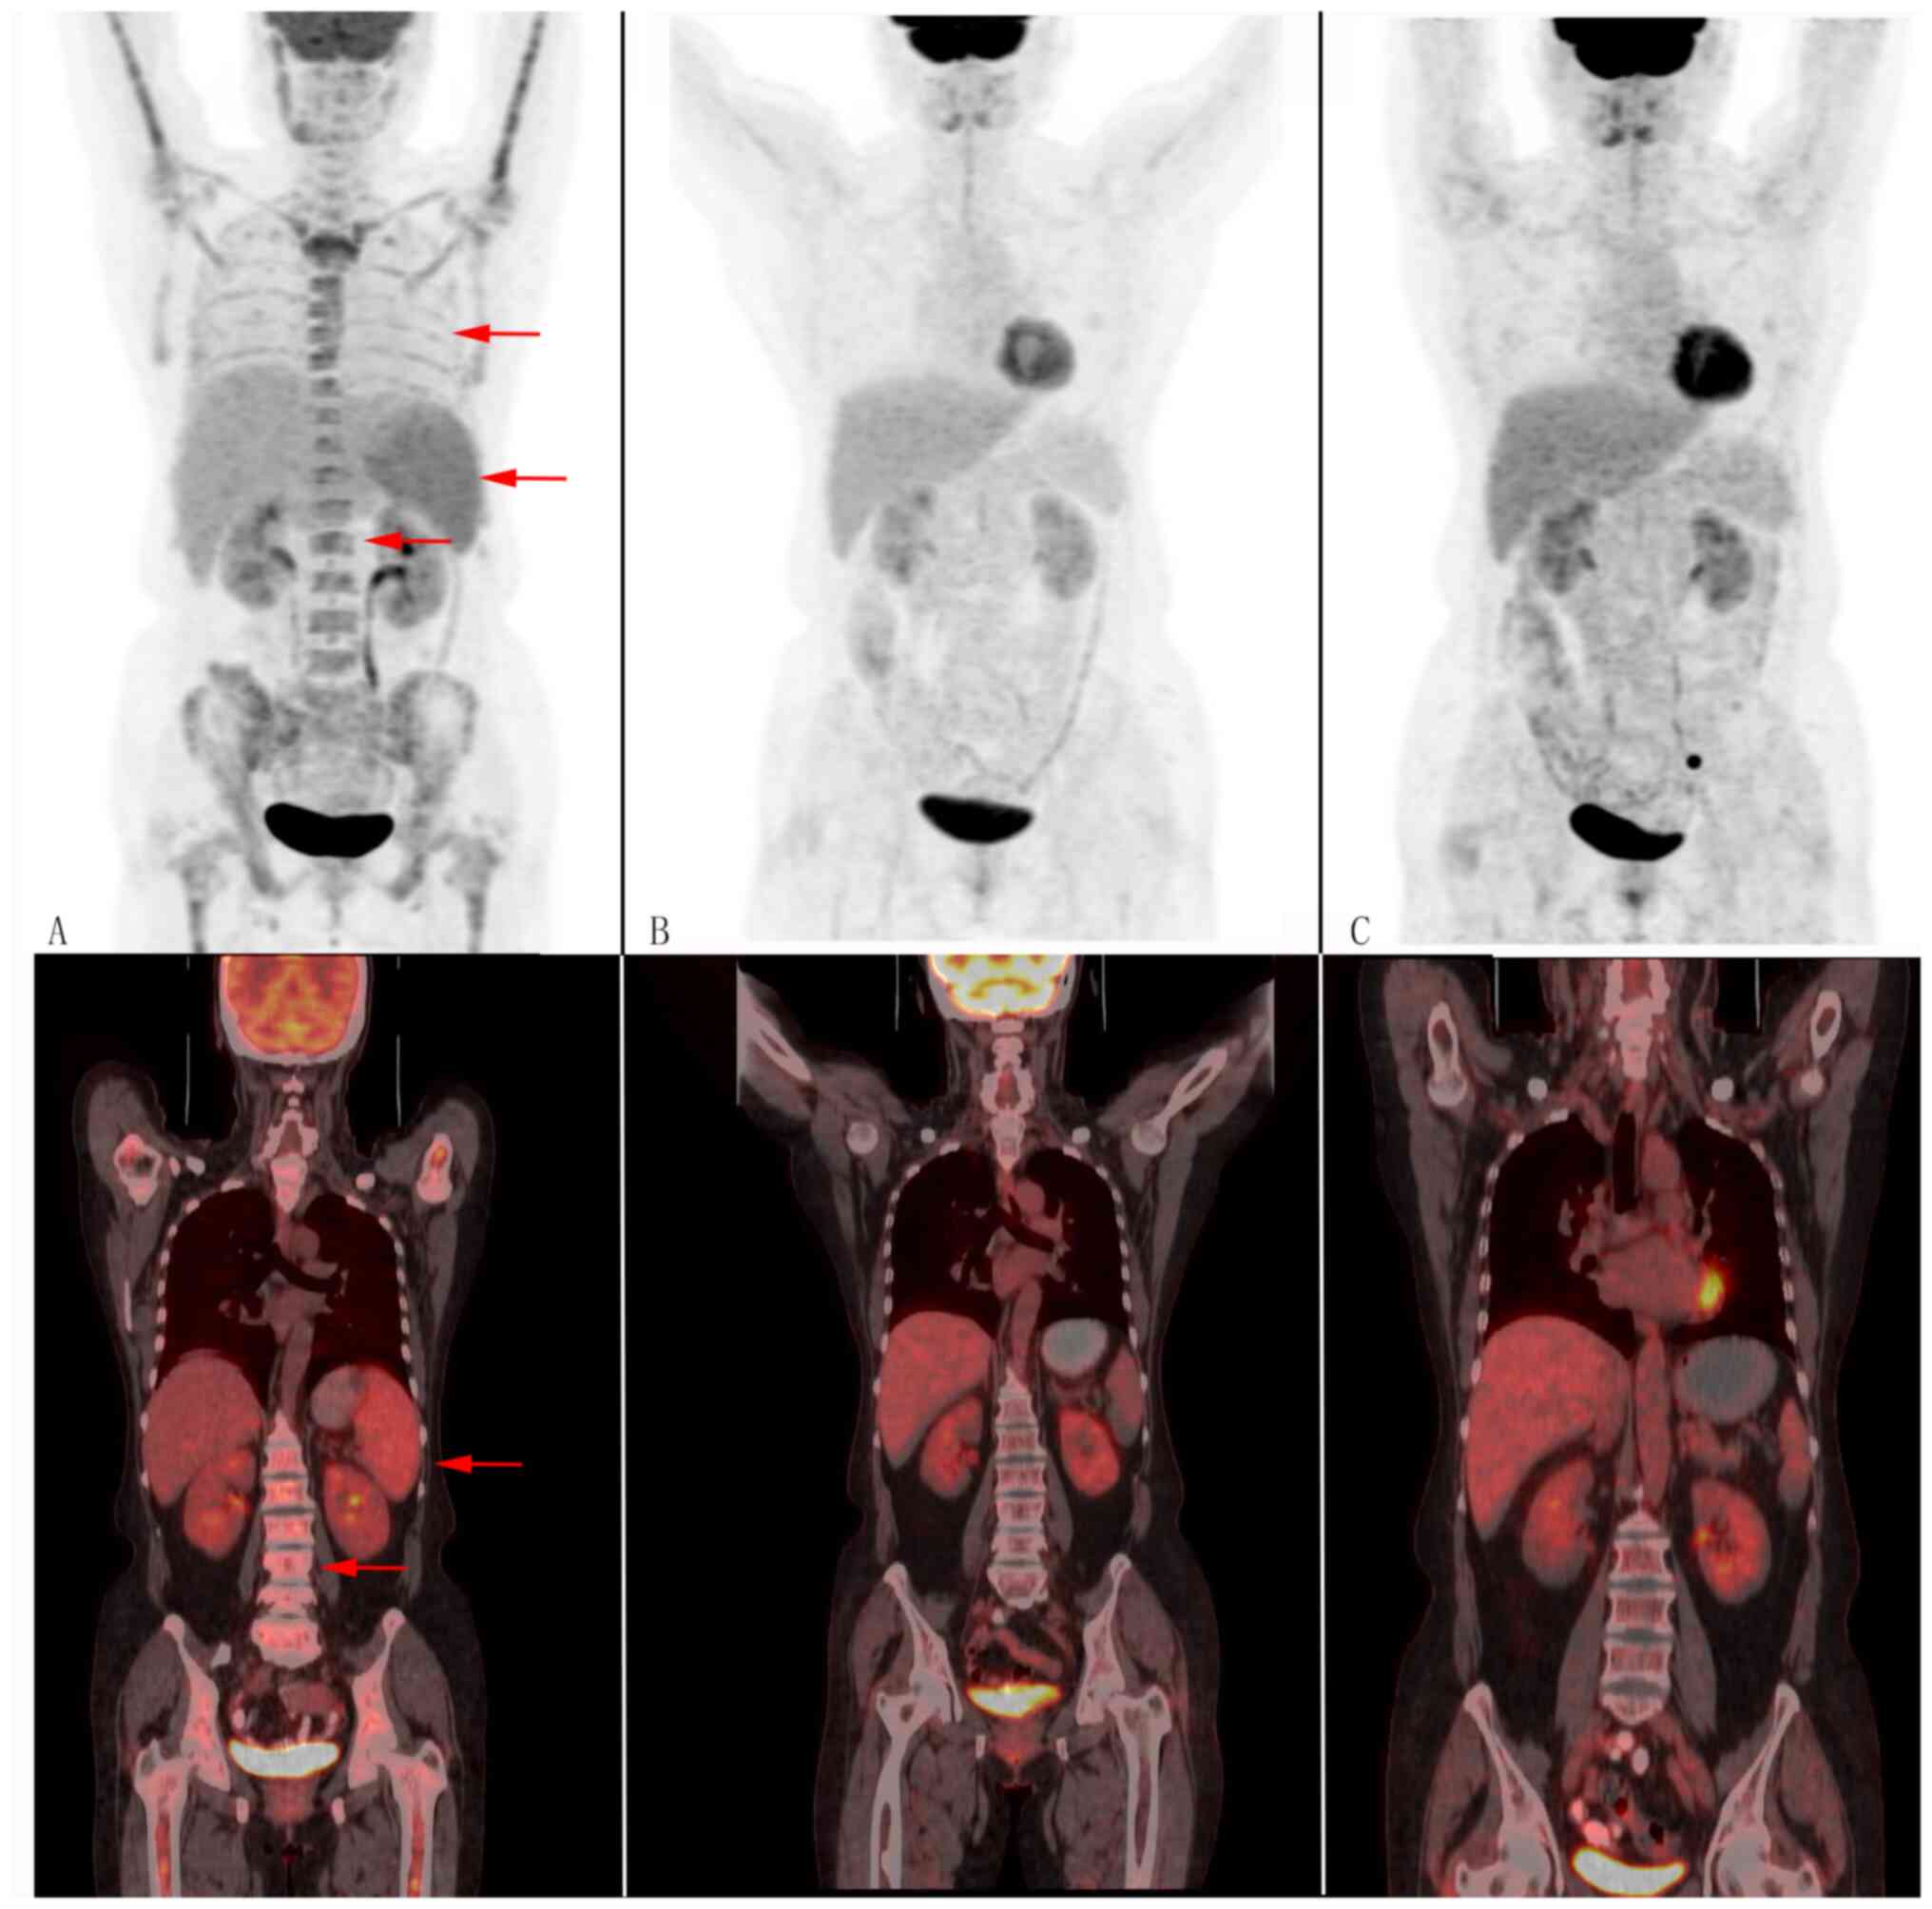

The main laboratory findings are shown in Table I and suggest Epstein-Barr virus (EBV) infection. An ophthalmologist diagnosed xerophthalmia. Bone marrow biopsy samples were positive for CD20 (Fig. 1) and BCL2 and C-myc large cells were identified within vascular spaces, resulting in a diagnosis of double-expression IVLBCL. Immunostaining also revealed that the tumour cells were positive for PAX-5, CD31, CD34, CyclinD1 and Mum1 (Fig. S1), and negative for CD10, BCL6 and CD30; the Ki-67 index was 80%. Flow cytometric analyses of bone marrow revealed positivity for CD20, CD22, CD79b and lambda chains and were negative for CD38, CD138 and kappa (Fig. S2). In addition, positron emission tomography/computed tomography (PET/CT) showed splenomegaly and hypermetabolism, and bilateral lung and bone marrow diffuse hypermetabolism, resulting in a diagnosis of IVLBCL before bone marrow biopsy (Fig. 2). Our patient thus met the five diagnostic criteria for hemophagocytic lympho-histiocytosis (HLH), namely fever, splenomegaly, cytopenia, ferritin ≥500 ng/ml, sCD 25 ≥2,400 U/ml and a bone marrow sample showing hemophagocytes (Fig. 1) (8). Cranial magnetic resonance imaging (MRI) revealed a hyperintense lesion in the central pons (Fig. 3). Thyroid ultrasound indicated hypoechoic thyroid nodules. Papillary thyroid carcinoma (PTC) was diagnosed by fine needle aspiration biopsy (Fig. 1). Immunofixation electrophoresis displayed M proteins positive and IgG kappa light chains (Fig. S3). Next-generation sequencing of bone marrow yielded mutations for the genes of DNMT3A exon13, DNMT3A exon8, FAT1 exon6 and CCND1 exon3. Nucleic acid extraction was performed using the Blood Genomic DNA Extraction Kit (0.1-1 ml; cat. no. YDP348-03; Tiangen Biotech Co., Ltd.). Nucleic acid quality inspection was performed using a NANODROP ONE (Thermo Fisher Scientific, Inc.) to measure the preliminary DNA concentration, A260/280 and A260/230, where A260 is the absorption wavelength of the highest absorption peak of nucleic acid and A280 is the absorption wavelength of the highest absorption peak of protein. A230 is the absorption wavelength of the highest absorption peak of carbohydrates.

Based on the aforementioned findings, the patient was diagnosed with HPS-associated IVLBCL (Ann Arbor IVB, IPI 3 scores) and PTC. On the second day of treatment with the HLH-1994 and ruxolitinib treatment protocol, the patient's high fever, which had consistently been present for more than a month, normalised. Tests for EBV were negative after treatment with acyclovir and one course of R-CHOPE therapy comprising rituximab, cyclophosphamide, hydroxydaunorubicin, vincristine, prednisone and etoposide [rituximab 600 mg, intravenous guttae (ivgtt): day 0 (D0); etoposide 0.1 g ivgtt: D1-2; cyclophosphamide 1,000 mg ivgtt: D1; doxorubicin liposomes 40 ms ivgtt: D1; vincristine 2 mg ivgtt: D1; and prednisone 100 mg p.o: D1-5]. After 4 courses of chemotherapy, a bone marrow biopsy showed an absence of tumour cells (Fig. 1). Throughout these 4 courses of treatment, PET/CT images showed complete remission (Fig. 2) and serum titres of cytokines normalised. The patient refused to consent for treatment of her PTC by thyroidectomy. At the time of submitting this article, the patient had undergone 8 courses of chemotherapy and 4 courses of intrathecal chemotherapy (methotrexate 10 mg) and PET/CT had shown a complete response (Fig. 2). She has been taking zanubrutinib 80 mg orally twice daily for 1.5 years and remains in remission.

A literature search revealed 8 previously reported cases of IVLBCL that involved the thyroid (9-16) (Table II). These patients presented with diverse symptoms and had poor prognoses. IVLBCL and PTC occurred concurrently in only 1 of these patients (10). In that patient, IVLBCL was initially diagnosed by PET/CT and subsequently confirmed by bone marrow biopsy. In our patient, fine needle aspiration biopsy of the thyroid revealed only PTC. PET/CT showed thyroid and lung hypermetabolism. The decrease in PET/CT metabolism after chemotherapy suggested that IVLBCL may had invaded the thyroid and lung. It was nto possible to confirm this because the patient did not undergo total thyroidectomy or lung biopsy. It has been reported that, even in the absence of neurological symptoms, ~90% of patients with IVLBCL have abnormalities on pre-treatment brain MRI and that hyperintense lesion in the pons on T2WI are potentially of diagnostic value (17). No brain lesions were definitively diagnosed because brain biopsy is difficult. In our patient, the hyperintense lesion revealed on a pre-treatment MRI had completely resolved by four courses of treatment.